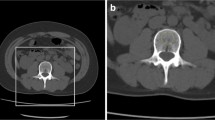

A deep learning algorithm of convolutional neural network (CNN) was used for the purpose. The method includes image segmentation, CNN learning, and a convolution-based regression model (DeepDXA) that links the isolated images of the femur bone to predict BMD value. Data were obtained in a single medical center from 2006 to 2018, with a total amount of 3472 pairs of pelvis X-ray and DXA examination within 1 year.